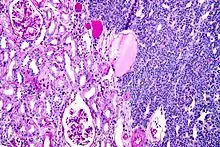

| Micrograph of a metanephric adenoma with structures reminiscent of those seen in papillary renal cell carcinoma. H&E stain. | |

Metanephric adenoma (MA) is a rare, benign tumour of the kidney, that can have a microscopic appearance similar to a nephroblastoma (Wilms tumours),[1] or a papillary renal cell carcinoma.

Metanephric adenoma is diagnosed histologically. The tumours can be located at upper pole, lower pole and mid-hilar region of the kidney; they are well circumscribed but unencapsulated, tan pink, with possible cystic and hemorrhagic foci. They show a uniform architecture of closely packed acinar or tubular structures of mature and bland appearance with scanty interposed stroma.[3][4][5][6][7] Cells are small with dark staining nuclei and inconspicuous nucleoli. Blastema is absent whereas calcospherites may be present. Glomeruloid figures are a striking finding, reminiscent of early fetal metenephric tissue. The lumen of the acini may contain otherwise epithelial infoldings or fibrillary material but it is quite often empty. Mitoses are conspicuously absent.[3][4][5][6][7] In the series reported by Jones et al. tumour cells were reactive for Leu7 in 3 cases of 5, to vimentine in 4 of 6, to cytocheratin in 2 of 6, to epithelial membrane antigen in 1 of 6 cases and muscle specific antigen in 1 of 6.[5] Olgac et al. found that intense and diffuse immunoreactivity for alpha-methylacyl-CoA racemase (AMACR) is useful in differentiating renal cell carcinoma from MA but a panel including AMACR, CK7 and CD57 is better in this differential diagnosis.[8] Differential diagnosis may be quite difficult indeed as exemplified by the three malignancies initially diagnosed as MA that later metastasized, in the report by Pins et al.[9]